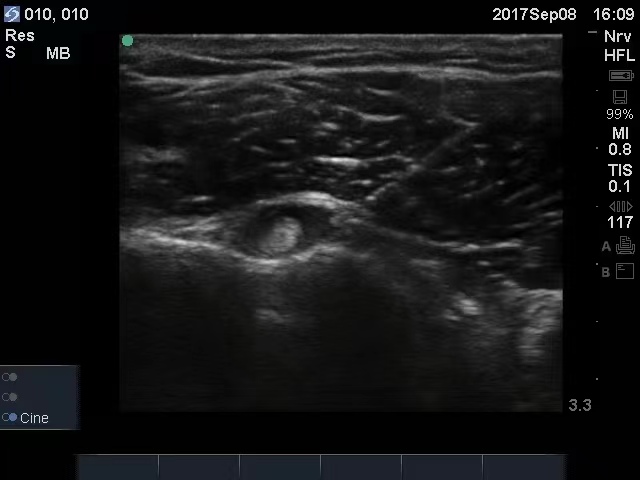

对该患者诊断明确后,我们对其采用基础用药方案:氟比洛芬凝胶贴膏加醋氯芬酸肠溶片进行抗炎止痛,并联合应用中枢性肌肉松弛药替扎尼定。 全身用药作用较慢,并不能够迅速消除该患者肩关节局部的炎症、水肿和疼痛,必须有一种方法能够直接作用于病变部位,快速改善症状,促进关节炎症的消除和肌腱损伤的修复。基于这些考虑,我们在超声引导下对患者进行肩关节注射治疗。 关于局部炎症损伤引起的疼痛,我们一般首选的局部注射药物是甾体类药物(曲安奈德、倍他米松或者地塞米松等)。 甾体类药物具有强大的抗炎作用,能够迅速消除炎症,改善水肿,减轻疼痛。但是,因为这个患者血糖控制不佳,可能针对其应慎用或者禁用甾体类药物。我们采用三氧治疗(又叫臭氧治疗)方法。三氧具有非常好的抗炎作用,它还能够氧化蛋白多糖,减轻滑膜水肿,并能够改善组织缺氧,直接止痛,是非常好的一个抗炎治疗方法。该患者进行三氧治疗后,炎症迅速消除,疼痛也明显缓解。 这个患者除了肩周炎,还有肩袖损伤,而肩袖损伤的修复相对困难。这些年来,在运动医学领域,PRP(富血小板血浆)注射治疗技术应用非常广泛,NBA(美国男子职业篮球联赛)湖人队球员霍华德就因为肩关节盂唇撕裂,接受了PRP注射治疗并取得了非常好的效果。PRP注射治疗是抽取患者自身血液,提取PRP,应用于患者自身,加速人体的自然愈合,促进骨和软组织再生。提取的这些PRP成分,不仅为组织修复提供了“浓缩的营养”,还为组织修复创造了更好的修复环境,能有效促进和加速组织修复。 我们借助疼痛科医生的“第三只眼睛”——超声,对该患者进行了三氧和PRP注射治疗。在超声下,可以非常清楚地看到病变部位,进行穿刺,能够准确地将穿刺针刺入相应的病变部位,达到靶点治疗的目的,并能够避免损伤血管神经等组织结构带来相应的不良反应。 这个患者最后的转归非常好,住院时进行了基础的药物治疗,在入院的第2天和第4天进行了肩关节三氧治疗后,疼痛评分迅速由中重度疼痛的6分降到了轻度疼痛的3分,然后在第6天和第13天分别进行了肩关节PRP注射治疗。出院时,患者的疼痛评分仅1分;一个月后随访,患者的疼痛基本消失。(作者供职于郑州大学第一附属医院)